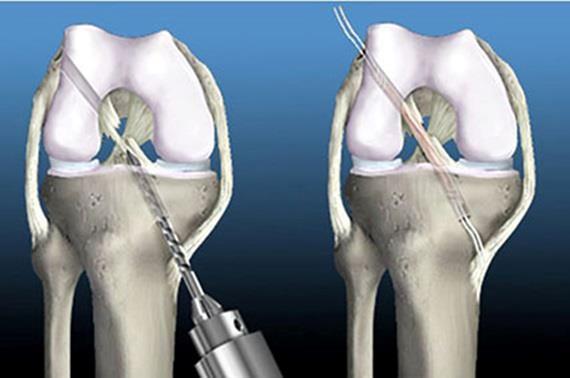

Cerrahi Tedavi Yöntemleri?

Ön çapraz bağ tamiri; kopan bağın uç uca dikilmesi ile tedavi edilebilen bir cerrahi yöntemi değildir. Kopan bağın yerine bağ nakli yapılarak tedavi edilebilmektedir. Bağ nakli için kullanılabilen 2 tip bağ vardır. Birincisi kişinin kendi vucudundan elde edilen bağlar(Otogreft), ikincisi ise kadavradan elde edilmiş olan (Allogreft) bağlardır. Allogreftler kuru greft ve taze dondurulmuş greftler olarak 2 tiptedir.

Vucuda uyum problemleri ve dayanıklılığının daha az olması nedeni ile günümüzde sıklıkla otogreftler kullanılmaktadır. Ancak bazı sporcularda mevcut yapıyı zayıflatmamak için allogreftler kullanılır.

Otogreftler vucutta bazı farklı bölgelerden elde edilmele birlikte bu gün sıklıkla uyluk arka adelesi tendonları(Hamstring) kullanılmaktadır.

Hamstring tendonları diz eklemi içerisine açılan kemik tüneller içerisine yerleştirilerek değişik yöntemler ile Artroskopik yöntem(kapalı ameliyat) kullanılarak kemiğe tutturulmaktadır. Tendonun kemiğe tespiti için birçok farklı materyal bulunmakta olup hangi yöntemin kullanılacağı cerrahın tecrübesine bağlıdır.

En sık rastlanılan komplikasyon greft alınan bölge ile ilgili ağrı ve kanamadır. Ameliyat sırasına ve sonrasında birtakım komplikasyonlar görülebilmekle birlikte sıklıkla; kanama, Ağrı, enfeksiyon, eklem sertliği ve konulan tendonun gevşemesi veya kompması meydana gelebilir